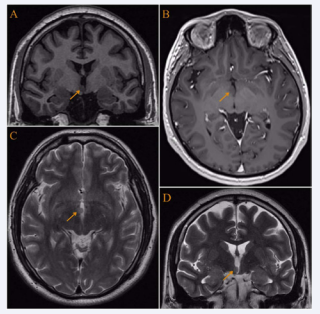

Neuroimaging: On conventional axial CT images, the diagnosis can be challenging, depending on slice position and thickness, although with more recent volumetric scans with coronal and sagittal reformats, the abnormality is easier to identify. Non-enhanced CT scan reveals a homogeneous nodule with obliteration of the suprasellar cistern and anterior 3rd ventricle, iso or hyposense compared with the grey matter. HH do not enhance on high- dose contrast-enhanced CT [45]. The MRI is the method of choice in suspected cases, pedunculated HH are shaped like a collar button on sagittal T1WI, extending inferiorly into the suprasellar cistern. Signal intensity is usually isointense to normal gray matter on T1WI and iso- to slightly hyperintense on T2/FLAIR (Figure 1).

MRI shows a type I hamartoma on the right side of the hypothalamus  (small arrows). (A) - Coronal T1WI shows a clearly isointense with gray matter  tumor. (B) - Axial T1WI after contrast administration shows a non enhancing  lesion. (C) - Axial T2WI shows the mass remains isointense with gray matter.  (D) - Coronal T2WI.

Figure 1: MRI shows a type I hamartoma on the right side of the hypothalamus (small arrows). (A) - Coronal T1WI shows a clearly isointense with gray matter tumor. (B) - Axial T1WI after contrast administration shows a non enhancing lesion. (C) - Axial T2WI shows the mass remains isointense with gray matter. (D) - Coronal T2WI.

The degree of T2 hyperintensity is directly related to the proportion of glial versus neuronal tissue in the lesion. HH do not enhance following contrast administration [45,46]. The MRI spectroscopy shows mildly decreased N-acetylaspartate and slightly increased choline, consistent with reduced neuronal density and relative gliosis. Myoinositol is elevated, which is consistent with increased glial component compared to normal brain [47,48]. Ictal FDG-PET scans in HH with GS are rare. Palmini et al., reported one patient who demonstrated ictal hypermetabolism localized to the region of the HH during gelastic status [23,49]. Ictal SPECT studies have clearly demonstrated HH hyperperfusion. In the three patients of Kuzniecky et al., there was in addition absent activation of the cortex but coactivation of the thalamus consistent with seizure propagation to the anterior nucleus of the thalamus via the mamillothalamic tract [50,51,49].